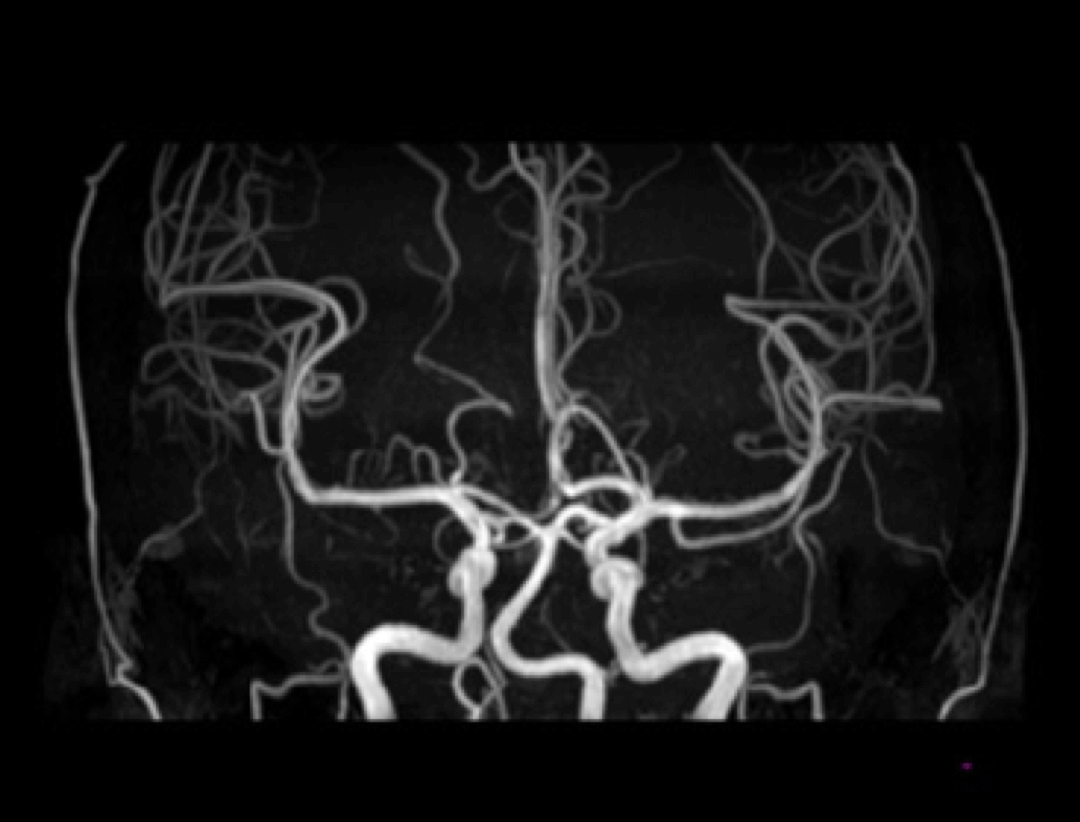

Neuro

Angiography